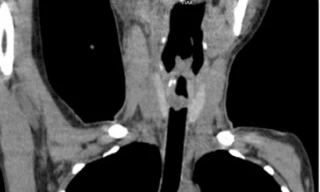

TPO - Được chẩn đoán bị hen phế quản nhưng điều trị trong thời gian dài không thuyên giảm khiến cô gái trẻ liên tục bị suy hô hấp, đe dọa tính mạng. Các bác sĩ Bệnh viện Quân y 175 đã phát hiện trong khí quản của bệnh nhi có khối u hiếm gặp đã phát triển lớn gây tắc hẹp đường thở.